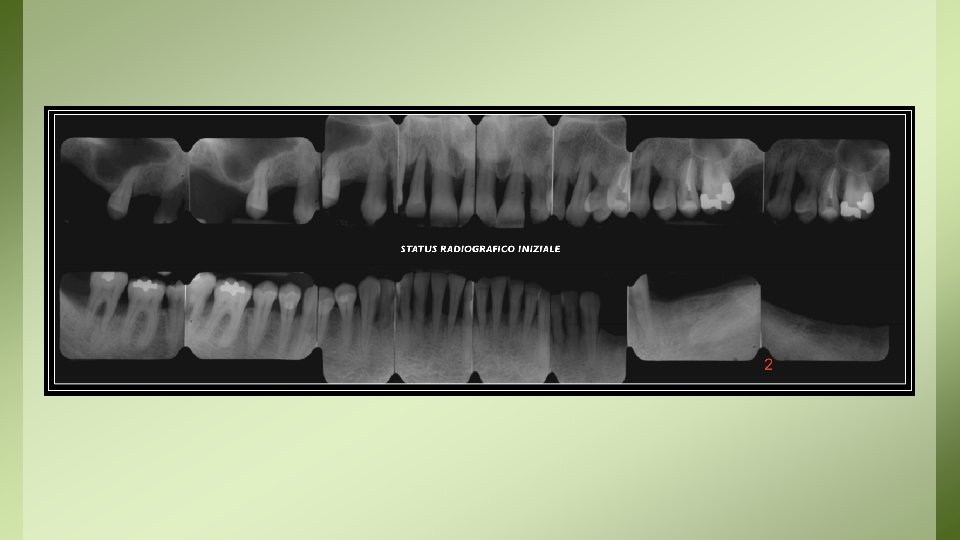

Documentazione Radiologica Sul tema della conservazione della documentazione di diagnostica per immagini, il D. M. del 14 febbraio 1997 (9)distingue: • a) documenti radiologici e di medicina nucleare, definiti come la “documentazione iconografica prodotta a seguito dell’indagine diagnostica utilizzata dal medico specialista nonché… quella prodotta nell’ambito delle attività radiodiagnostiche complementari all’esercizio clinico”; • b) resoconti radiologici e di medicina nucleare, cioè i “referti stilati dal medico specialista radiologo o medico nucleare”.

• La documentazione radiologica di cui al punto a) deve essere conservata (su pellicola radiografica, supporto cartaceo o elettronico) per un periodo NON inferiore ai 10 anni, ed essere resa disponibile e/o consegnata su richiesta al paziente o agli aventi diritto. – NOTA: per le CBTC deve essere assicurata adeguata archiviazione e conservazione del consenso informato per un periodo di almeno 5 anni e di tutte le immagini per non meno di 5 anni (come da raccomandazioni ministeriali del 2010) • La documentazione radiologica di cui al punto b) va invece conservata illimitatamente.